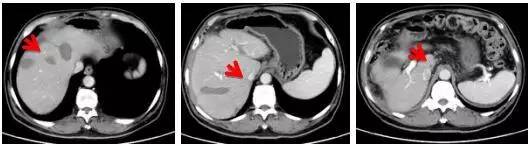

消融术后继续靶向治疗联合化疗,病情稳定未有发展

2016.7.15

2016.9.24